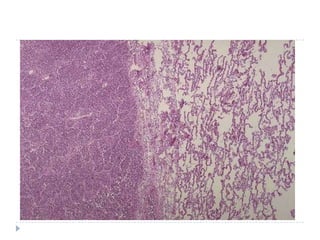

LOBER PNÖMONĠ

BRONKO

PNÖMONĠ

Toplum içinde edinilenakut pnömoni morfoloji  Bronkopnömoni: yama tarzında konsolidasyon  Lober pnömoni: bir lobun tamamının tutulumu  Konjesyon  Kırmızı hepatizasyon  Gri hepatizasyon  Rezolüsyon  *Klinik açıdan önemli olan etkenin belirlenmesi ve hastalığın yayılımının belirlenmesidir